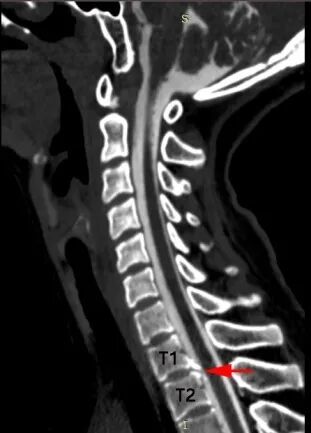

江女士的脊柱磁共振检查 可见第1、2胸椎之间有“骨刺”形成(红箭头) 刺破硬脊髓膜,造成脑脊液外漏(蓝箭头) 站立时头痛,躺下头不痛 警惕低颅压 浙江大学医学院附属邵逸夫医院神经内科副主任王谨主任医师解释: 自发性颅内低压是由于脊髓脑脊液渗漏,导致脑脊液容量减少所产生的。 我们的脑子和脊髓腔是一个密闭的囊腔,脑脊液充满在囊腔中起到了托浮作用,避免脑神经受到震荡。 一旦脊髓部位的囊腔(硬脊膜)发生破口,导致脑脊液渗漏、容量减少,就会导致低颅压。 低颅压最常见的表现是:站立时头痛,躺下头痛缓解。但部分患者可发生颅内出血、脑子下沉等严重并发症,威胁生命。

骨刺刺破硬脊膜,导致脑脊液外漏的示意图